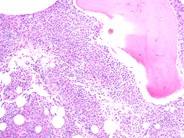

The patient is a 10 month old Caucasian male with a history of recurrent upper respiratory infections and otitis media since birth. His CBC at this time included a H/H of 10.9g/dl/32.4%, platelet count of 280,000/ul and a WBC of 3840/ul with a differential of 25% monocytes, 70% lymphocytes, 4% eosinphils, 1% basophils and 1% neutrophils. His ANC was 38/ul. After an extensive evaluation he was diagnosed as having congenital neutropenia consistent with Kostmann's syndrome. The peripheral smear confirmed the leukopenia and almost complete absence of neuutrophils. A single hyposegmented PMN can be seen in this view.